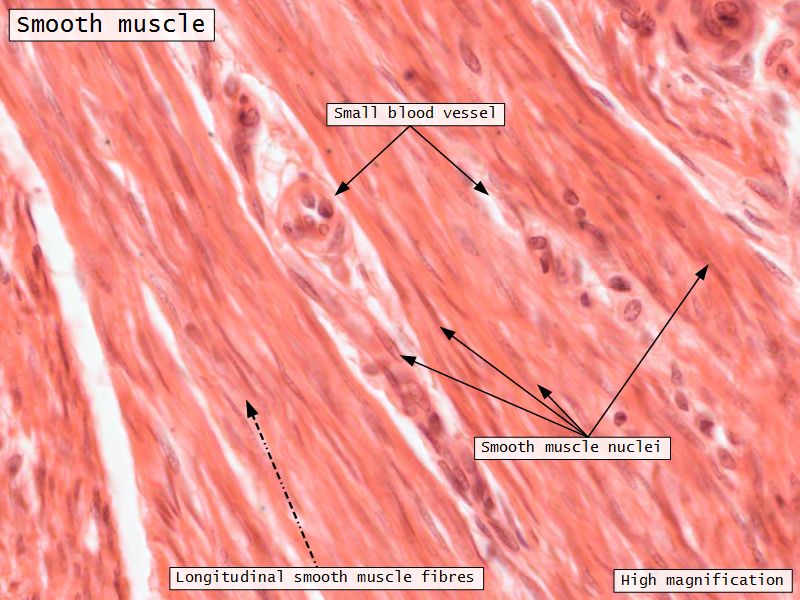

Myometrium

- 3 layers indistinct smooth

- Inner longitudinal/oblique

- Central circular

- Large blood vessels

- Stratum vasculare

- Outer longitudinal/oblique